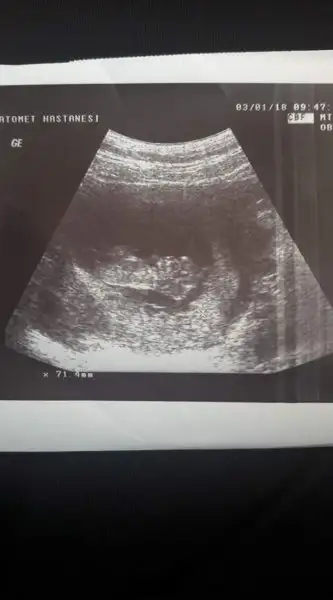

Bende pko var Cnm altı ay dur istiyorduk ovulasyon testiyle takip ettim günümü yumurtlama gününden bi gün önce ve sonra ilişki oldu öncesinde beş gün olmadı eşim yoktu ama ben le onla alakası yok tamamen nasip Cnm